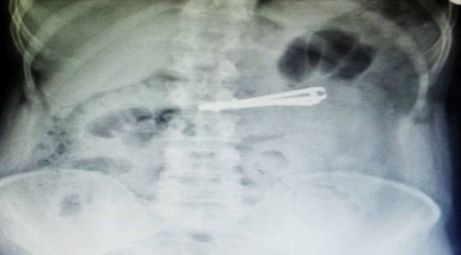

Siirt'in Kurtalan ilçesinde yaşayan ve doğuştan ağır mental retardasyon (zeka geriliği) hastası Mutih Akurt (42), elindeki tırnak makasını yuttu.

Hastanın midesindeki tırnak makası, Genel Cerrahi Uzmanı Dr. Yasemin Küçük'ün yaptığı endoskopiyle çıkarıldı.